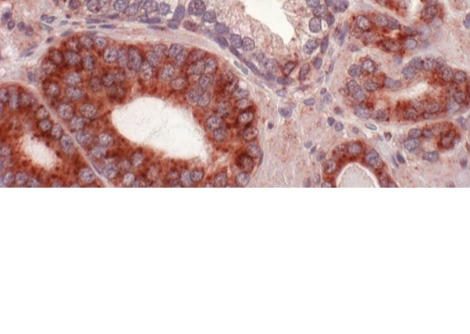

لإنشاء شاشة عرض حية، قام الباحثون بتعديل الخلايا الجذعية للبشرة وراثيًا بحيث تستجيب لإشارات الالتهاب داخل الجسم. عند تنشيط مسار رئيسي مرتبط بالالتهاب، يُعرف باسم NF-κB، تُنتج الخلايا المُهندسة بروتينًا فلوريًا أخضر.

ثم استُخدمت هذه الخلايا المُعدّلة لزراعة أنسجة جلدية، زُرعت على فئران. بعد التئام الطعوم واندماجها مع الأنسجة المحيطة، تصرفت البشرة المُهندسة بشكل مشابه للبشرة الطبيعية، باستثناء فرق جوهري واحد. فعندما يحدث التهاب داخل الجسم، تبدأ المنطقة المزروعة بالتوهج باللون الأخضر.

يُترجم هذا التوهج إشارة جزيئية غير مرئية إلى إشارة مرئية، مما يسمح بقراءة النشاط البيولوجي الداخلي مباشرةً على سطح الجلد. ولأن المستشعر مصنوع من خلايا جذعية حية، فهو لا يعتمد على الإلكترونيات أو مصادر الطاقة أو الاستبدال الدوري. ومع تجدد الجلد بشكل طبيعي، تستمر الخلايا الجذعية المُهندسة في إنتاج خلايا استشعار جديدة.